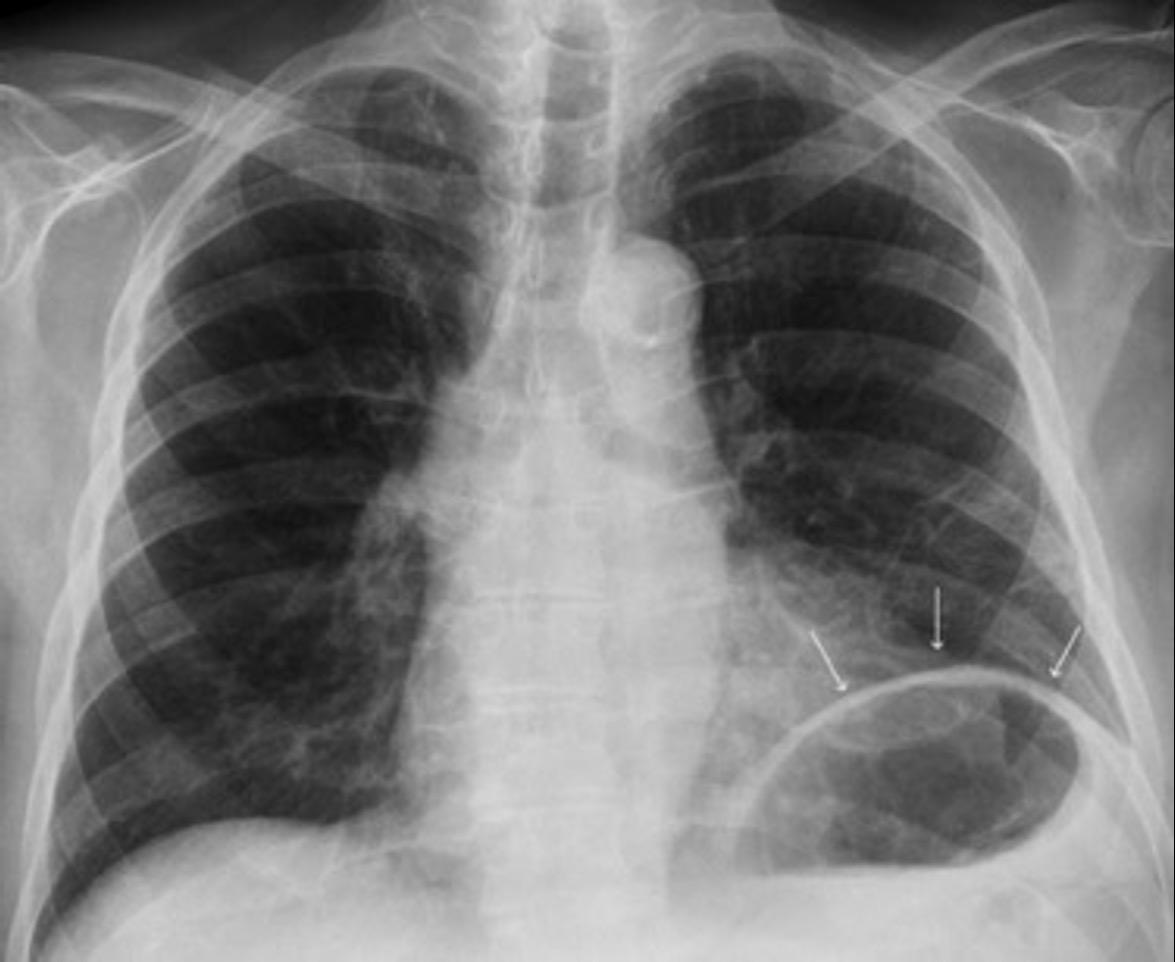

T. mixto de células germinales del testículo izquierdo

Nódulos pulmonares múltiples. (flechas verdes). Masas paratraqueales. (flechas amarillas). Dudoso ensanchamiento retrocrural (flechas negras). sigue….

Ttawfik A et al. Trans-diaphragmatic Pathologies: Anatomical Background and Spread of Disease on cross-sectional Imaging. Current Problems in Diagnostic Radiology. 2021.

T. mixto de células germinales del testículo

izquierdo Metástasis pulmonares. (flechas verdes). Ganglios paratraqueales. (flechas amarillas). Ganglios retroperitoneales (flechas negras)

Tawfik A et al. Trans-diaphragmatic Pathologies: Anatomical Background and Spread of Disease on cross-sectional Imaging. Current Problems in Diagnostic Radiology. 2021.